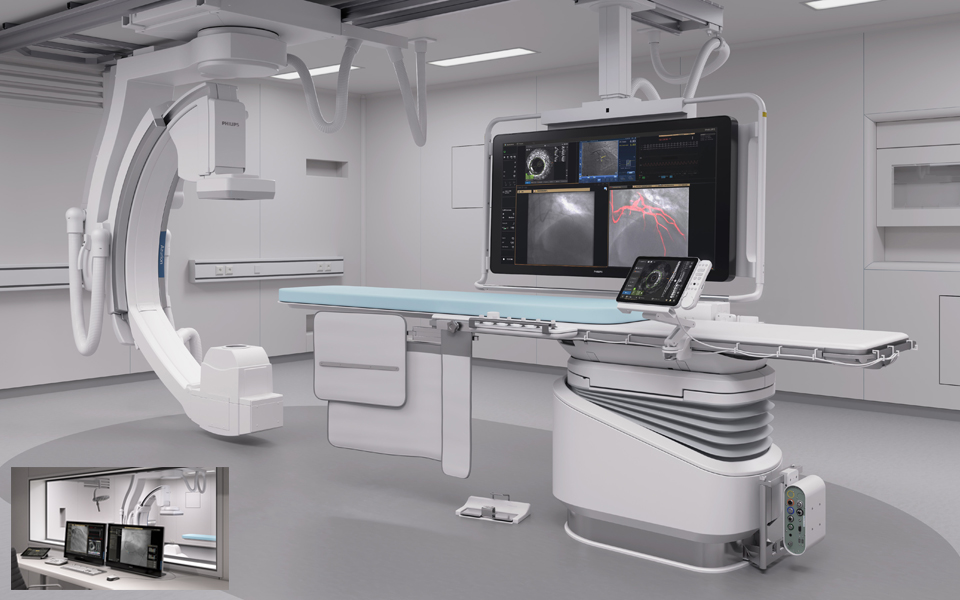

Image Guided Therapy System — Azurion

Azurion provides the ability to treat one more patient per day, reducing procedure time by 17%* with optimized workflow options in interventional therapy and clinical software.

Azurion 7 M12

Experience outstanding interventional cardiac and vascular performance on the Azurion 7 Series with 12'' flat detector. This industry leading image-guided therapy solution supports you in delivering outstanding patient care and increasing your operational efficiency by uniting clinical excellence with workflow innovation. Seamlessly control all relevant applications from a single touch screen at table side, to help make fast, informed decisions in the sterile field.